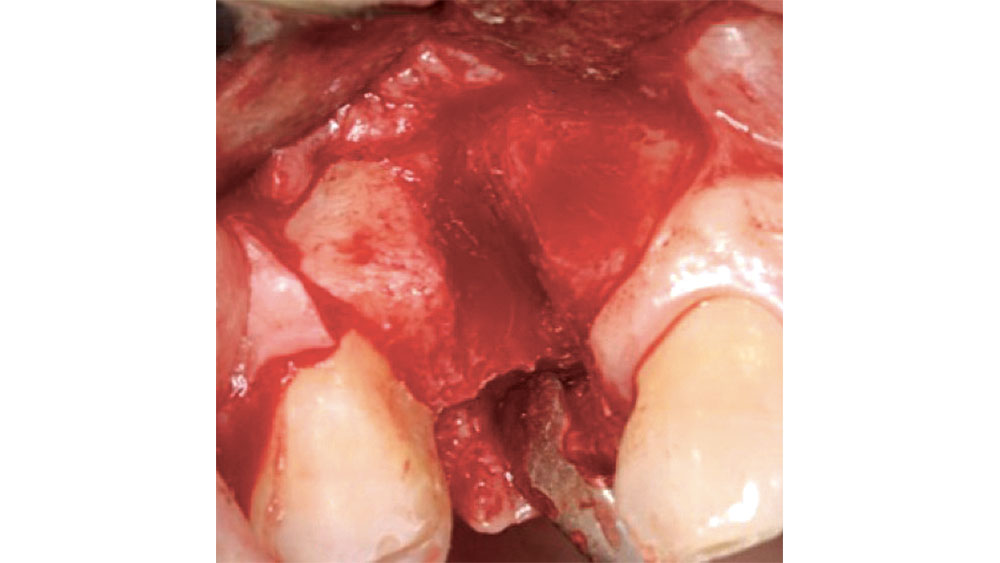

THREE-, TWO- AND ONE-WALLED EXTRACTION SOCKETS

When more than one bony wall is missing, there is a greater need for extensive bone grafting, which has traditionally involved the use of autogenous bone harvested from the mandibular ramus, mandibular symphysis or maxillary tuberosity. Increasingly, these defects are grafted with allograft to simplify the surgical procedure. If bone grafting in these types of extraction sockets is not performed, extensive loss of bone will result, along with soft-tissue loss, which leads to esthetic issues. Three-, two- and one-walled defects are highly compromised situations that usually involve through-and-through defects and are highly unpredictable (Fig. 6).